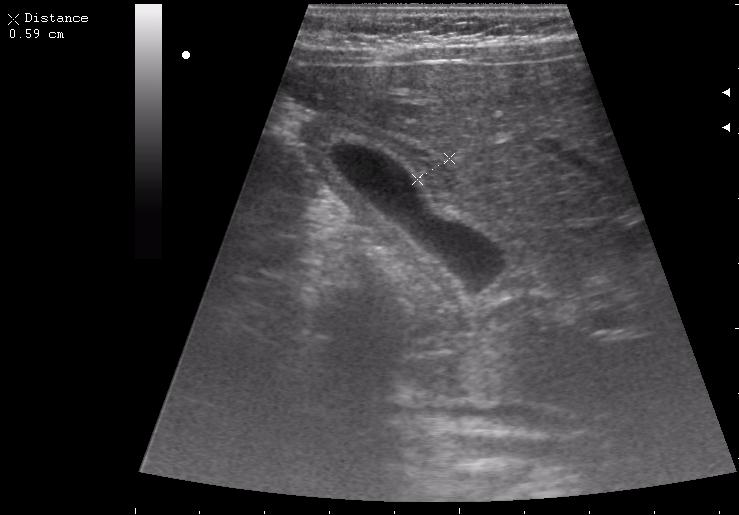

8-ми месячная девочка

По моему имеется утолщение стенки ж.пузыря по переднему контуру с частичным прерыванием наружного слоя(что-то врастает в стенку?Рядом печень имеет измененую структуру в виде некоторой неоднородности?)Надо исключить опухоль методом КТ

Имхо отек стенки. Наиболее частая причина - гепатит, также встречалось такое при психогенной анорексии (безбелковый отек).